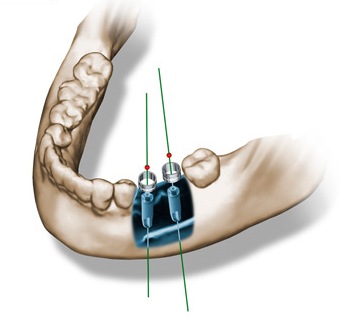

A custom designed surgical template is created, based on our exact planning. We know the final position of the implants before we start. This allows the laboratory to make the prosthetic solution beforehand, so it can be delivered to the patient during the actual surgery.

With NobelGuide™ the placing of the implant, abutment and restorative crown or bridge is simultaneous. It is applicable to any patient indication, by using either conventional modeling or computer aided-3D design – NobelGuide™ shows you the exact position and depth of the implants before surgery.

This information enables Nobel Biocare to produce a surgical template which guides the flapless procedure from start to a completely successful placement.